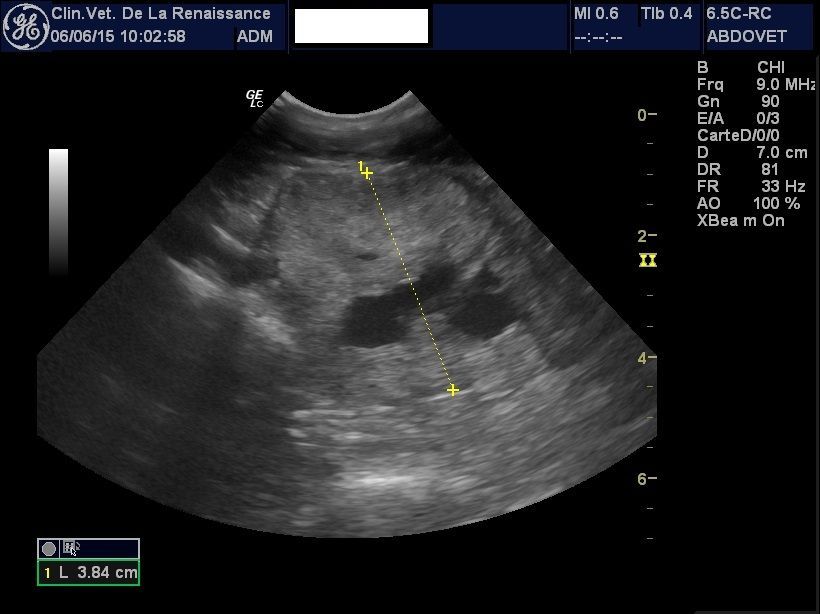

L'échographie

La clinique est équipée d'un échographe pour l'exploration de la cavité abdominale et de ses organes. Nous pouvons réaliser une échographie ciblée sur un organe ou sur l'ensemble des organes abdominaux, dans le cadre d'un diagnostic ou le suivi d'une pathologie ou d'une gestation. Un doppler permet dans le cadre de la gestation de mesurer la fréquence cardiaque des chiots. L'échographie peut être réalisée avec ou sans anesthésie générale en fonction de l'animal.